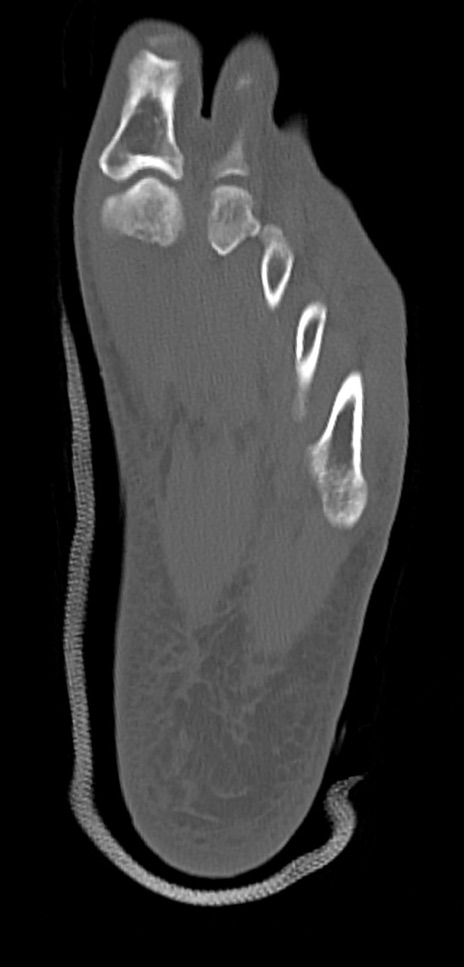

左足関節CT

矢状断像